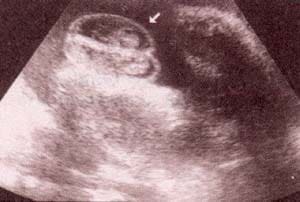

Diagnóstico Prenatal -  genitales externos xx Diagnóstico Prenatal -  genitales externos xx

fig. 49. – (c). 30 semanas. labios. fig. 49. – (d). 38 semanas. labios mayores (1) nótese la hipertrofia del clítoris (2).